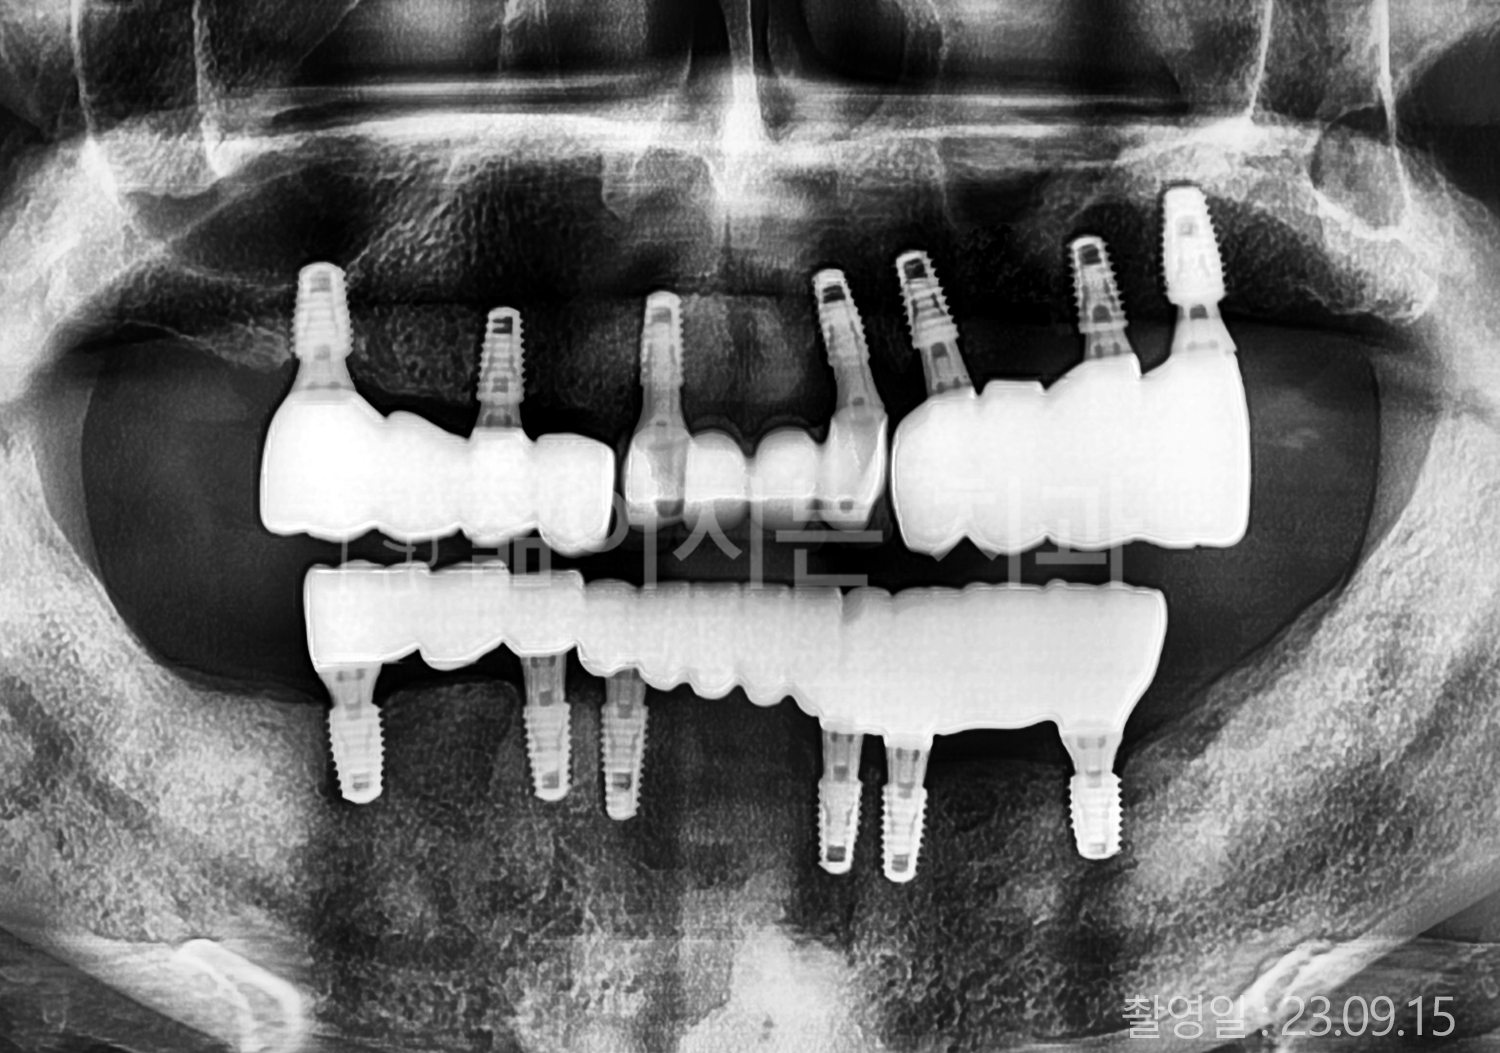

• 50대 전체치아 10개 이상 임플란트

• 50대 고혈압, 고지혈증 전체치아 10개 이상 임플란트